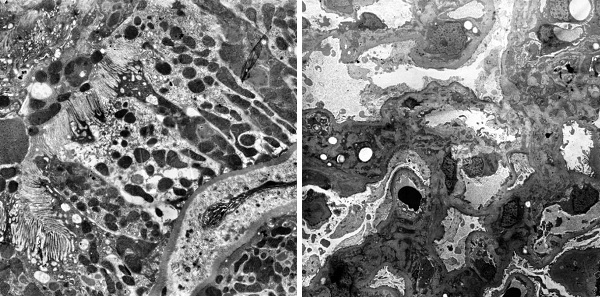

图2 电镜载网上的病理组织切片样品(SmartView背散射电子图像)

图3 利用SmartView对病理组织切片样品进行成像(中倍STEM像)

项目从医院病理科电镜病理检测存在的仪器维护成本高、操作复杂、通量低、人力成本高等痛点出发,成功研制了针对病理组织切片样品的高通量扫描透射电子显微镜SmartView(图1),发明了载网托盘和新型的装载方式(图2),一次可以装载500个病理切片载网,实现了8K*8K的高速扫描透射成像能力,仪器成像分辨率优于1.1nm,可以进行病理组织切片样品高速和高质量成像(图3,图4),将有效推动生物医学病理电镜检测快速发展。